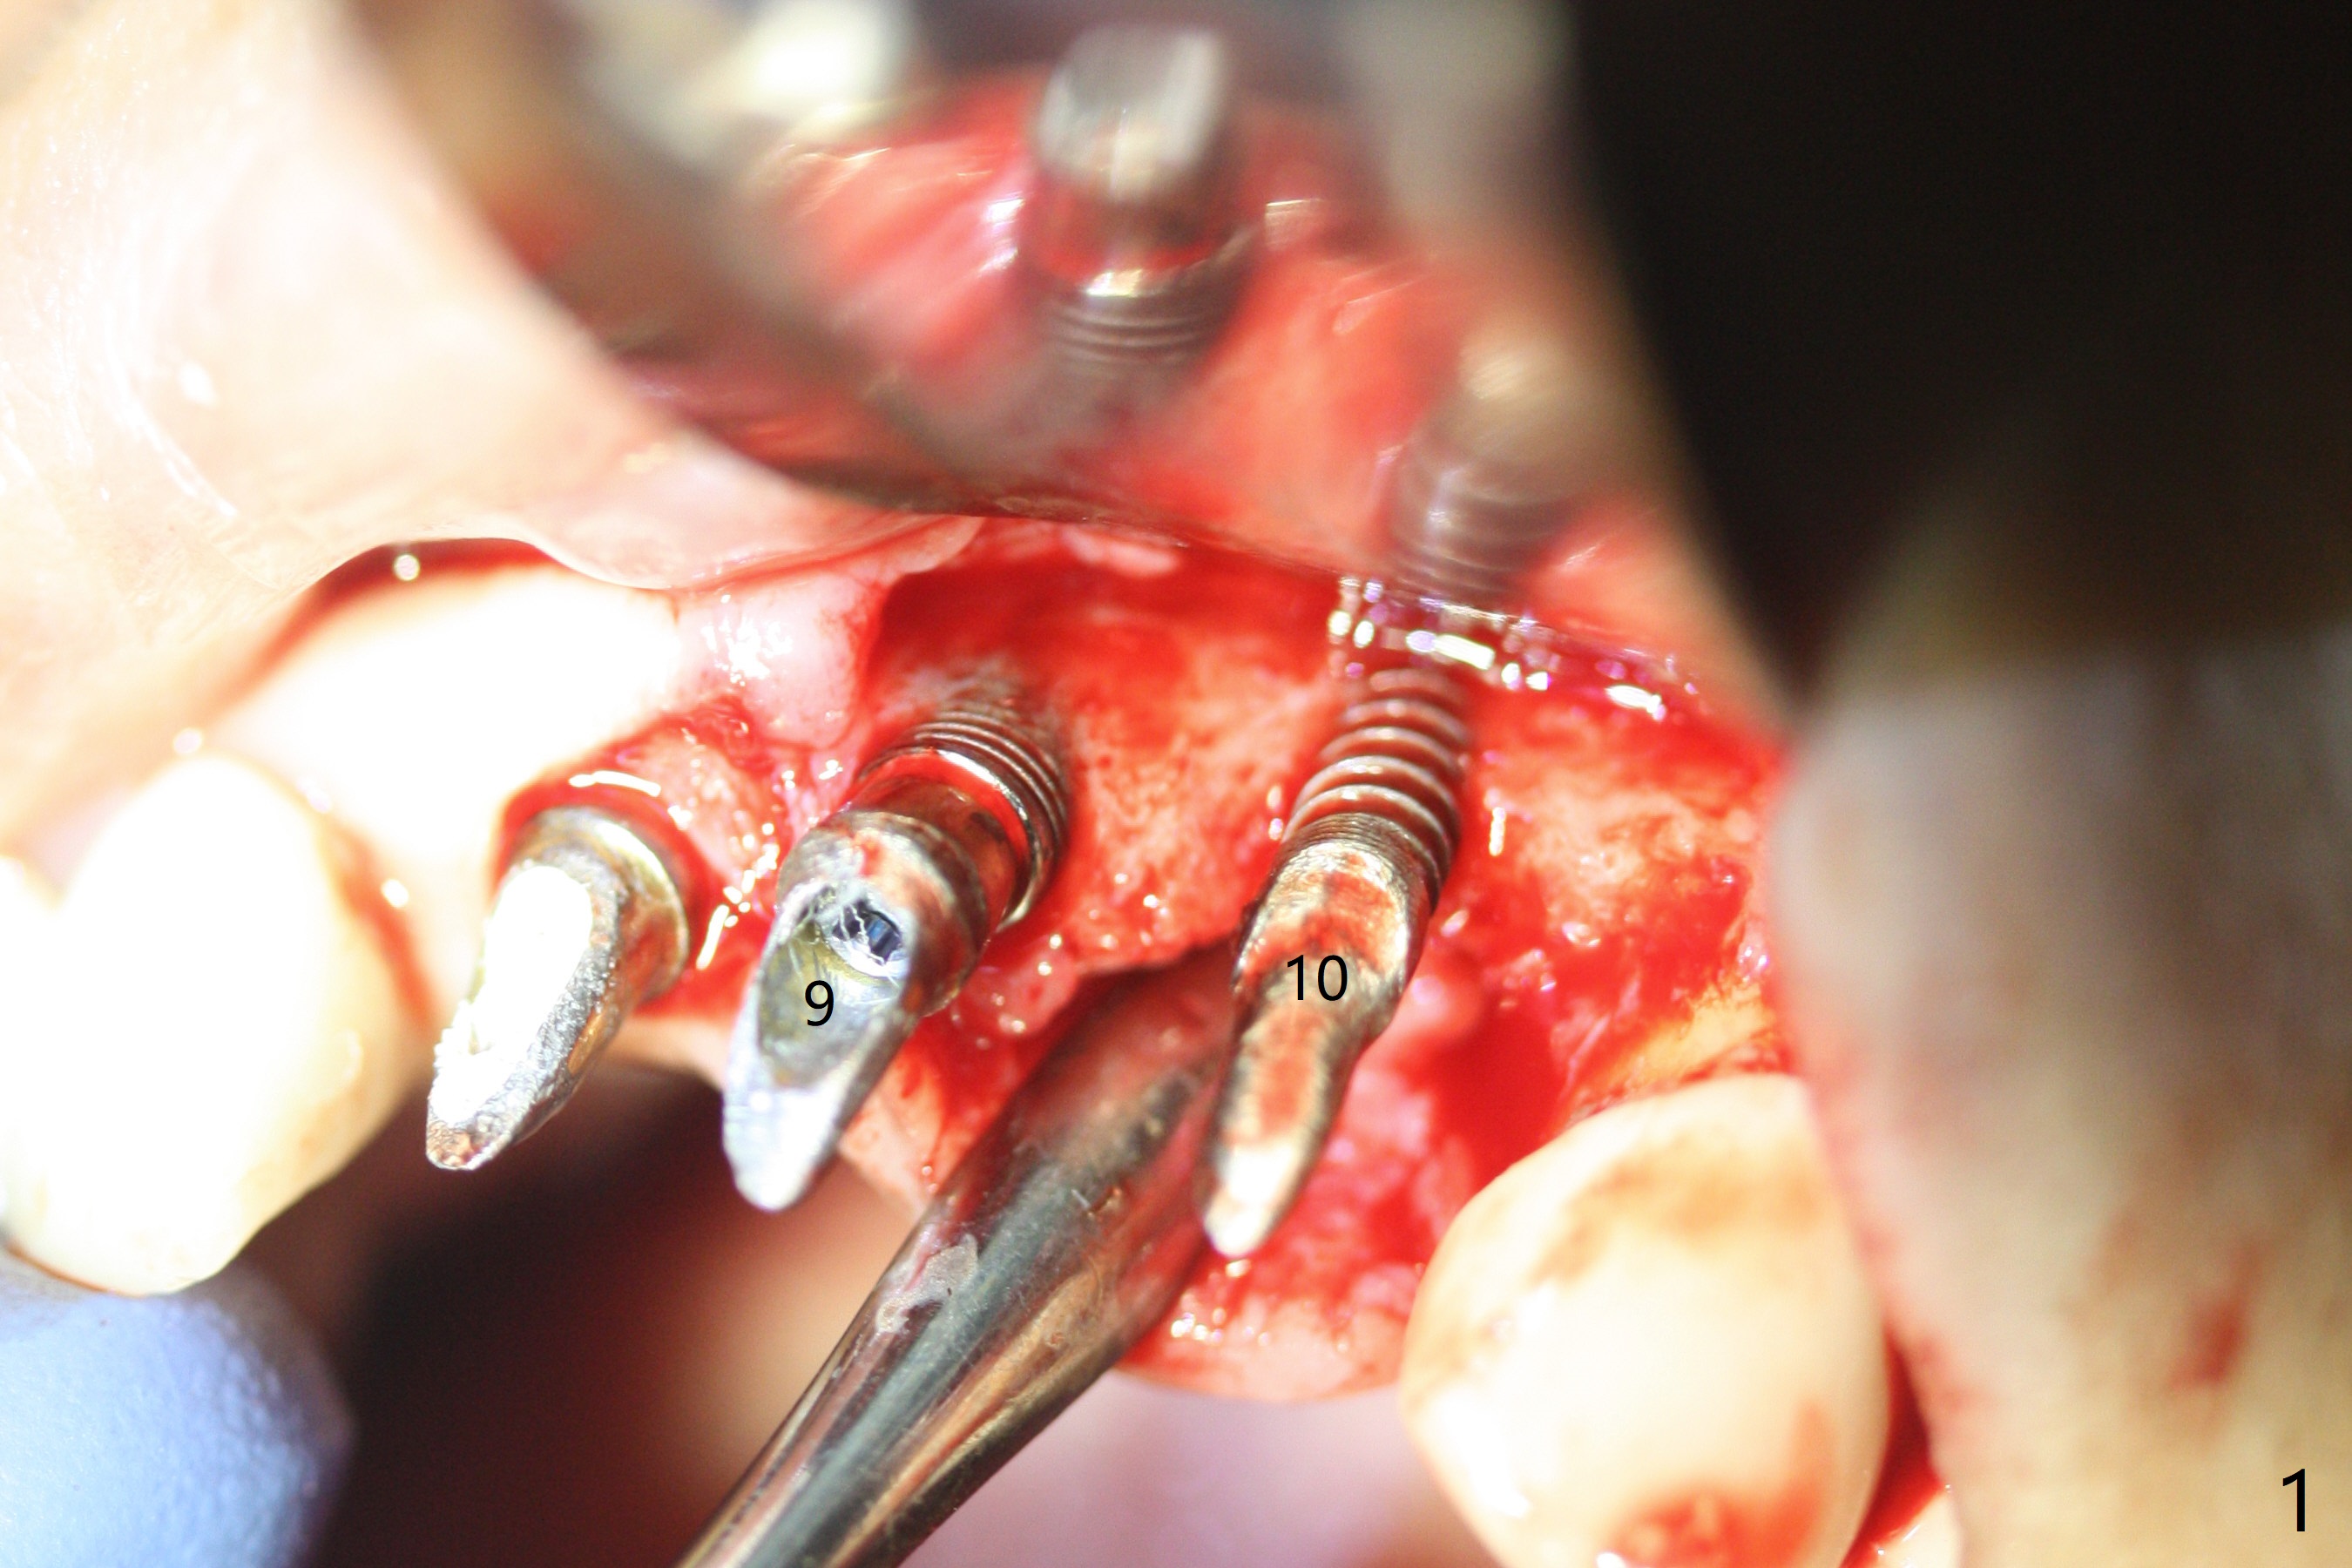

M

Incision shows exposure of microthreads at #9 and major threads at #10 due to buccal placement (Fig.1). There is bone palatal to the implant at #10 (Fig.2 P), to which a new implant will move. After implant removal, a narrower 1-piece implant (2.5x14(4) mm) is placed palatally at #10 (Fig.3,4) in combination of guide and free hand. At the site of #9 after implant removal, the guide is not used; a 3x17 mm angled 1-piece implant is placed with bad trajectory (Fig.5,6). After re-adjustment (Fig.7), the implant is placed at the right orientation (Fig.8). It appears that the guide is helpful. Allograft is placed mainly buccally (Fig.9,10 *), followed by a piece of collagen membrane (Fig.11). After tension release, flaps are approximated (Fig.12). The buccal gingiva at #9 and 10 recede nearly 2 months postop (Fig.13). Less recession at #9 is associated with more inflammation (Fig.14). The margin of the provisional is adjusted for gingival margin down growth and easy self cleaning with Water Pik (Fig.15). One month later, the gingival inflammation reduces, while there is no obvious buccal collapse (Fig.16,17). Impression is taken after laser gingivectomy nearly 4 months postop (Fig.18). While the gingiva around the implant at #9 is inflamed (periimplantitis?), the gingival cuff at #10 is well formed 5.5 months postop immediately before cementation (Fig.19). The buccal concavity at #10 is minimal (Fig.20). The gingival inflammation at #9 will be hopefully resolved after cementation of the final restorations (Fig.21). There appears to be new bone formation around the coronal implant threads 5.5 months postop (immediately post cementation, Fig.22). The microthreads at #9 may be not covered by the bone, the reason for the gingival erythema. The redness at #10 is asymptomatic 5.5 months post cementation (Fig.23). 粘固后两年牙槽嵴骨质并没有再生(图二十四),说明第一术中植体必须植入骨下(基台部分要长,否则难于修复),第二牙槽嵴处不应该有压力,植入2.5毫米植体,最后钻头应该是2.5毫米,骨下1-3毫米(尝试项目)。